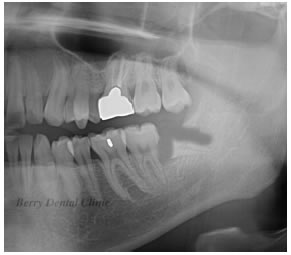

親知らずを1、2、3、と番号順にカットしていきます。

順番に取り除いていきます。

この画像では慎重に3の部分取り除きました。

約3ヶ月から6ヶ月後にはこの画像のように骨も綺麗に再生させれてきます。